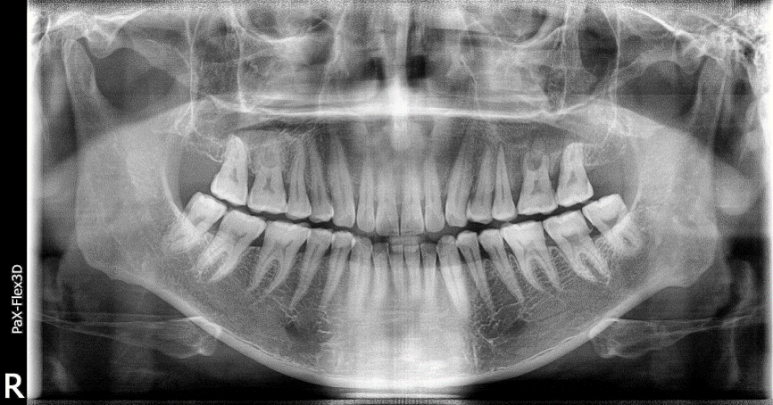

32세 여성 (2021-06-02)

치아 발치 후 오랜 기간 방치해서 인접 치아가 빈 공간으로 기울어진 상태

그래서 너무 오랫동안 기다렸다가 시술을 하게 되면 뼈와 잇몸은 잘 아물었을 수는 있어도

주변 치아들의 움직임 때문에 교합이 안 좋아져서 오히려 나중에 주변 치아들의 치열을 치료하거나 교정해야 하는 문제가 생길 수 있습니다.